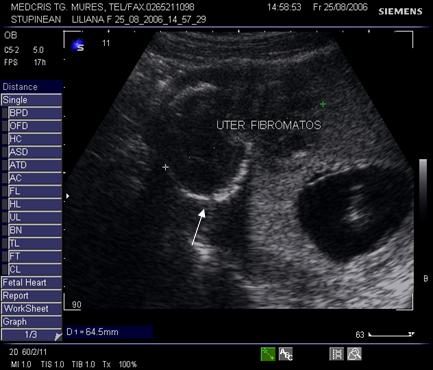

9.Sarcina si fibromul uterin

Cea mai comuna tumora uterina - leiomiomul - poate fi detectata si masurata inca de la inceputul sarcinii. Fibromul poate complica sarcina in functie de marime si pozitie. Nodulul subseros pediculat foarte rar se poate complica, in schimb nodulul submucos sau intramural creste riscul de avort spontan sau nastere prematura, dar peste 75% din aceste paciente duc sarcina la termen. Cea mai frecventa complicatie a fibromului in sarcina este necroza aseptica (25%) de obicei moderata, ea poate aparea si in lauzie. Cresterea fibromului in sarcina a fost notata in circa 22% dintre fibroame.[12]

Fibromul apare de obicei hipoecogen in uterul gravid, trebuind masurat si observat pe parcursul sarcinii.

Fig nr. 91. Nodul fibromatos submucos si sarcina

Fig. nr. 92. Nodul fibromatos intramural hipoecogen,

alaturi de sarcina de 12 saptamani